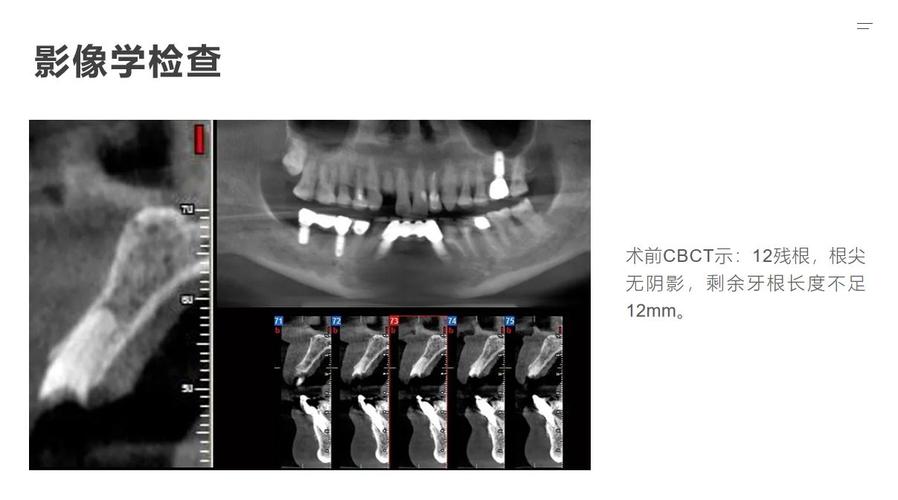

别怕检查,CT是“透视眼”:种牙前一定要拍CBCT,它能清晰显示牙槽骨的情况,比如骨量够不够、有没有神经血管,医生才能制定最适合你的方案,我邻床有个阿姨,因为没拍CT,直接种导致神经受损,半边脸都麻了,所以千万别省这一步。